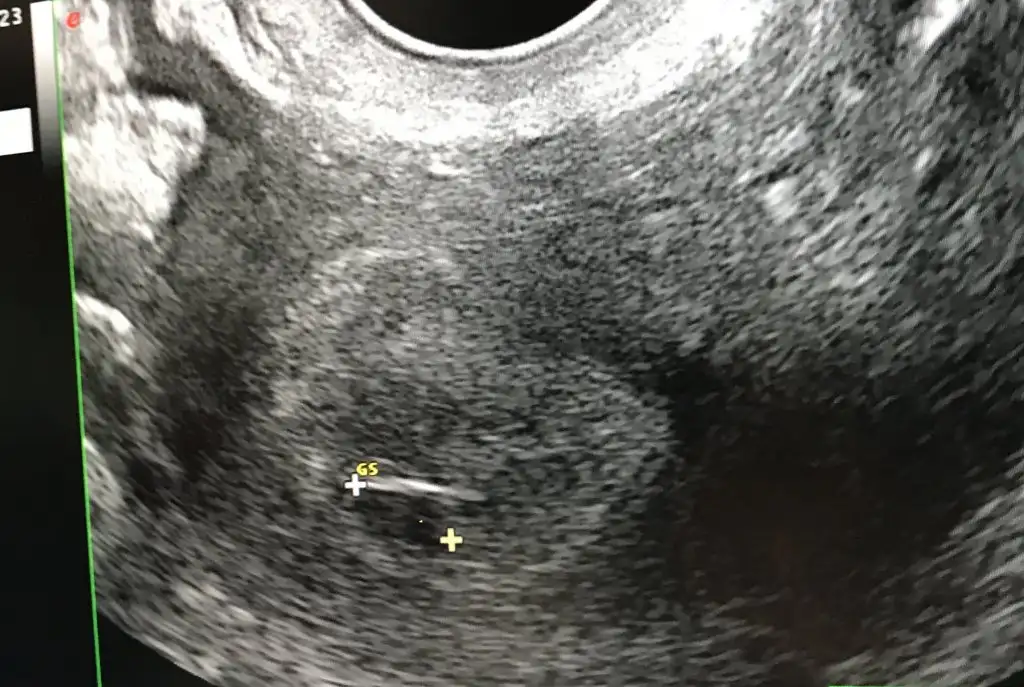

Merhaba 5 haftalık vajinal muayene☺️

Bakabilir misiniz?

A0D39284-8144-407B-B8F9-886AD0253D31.webp